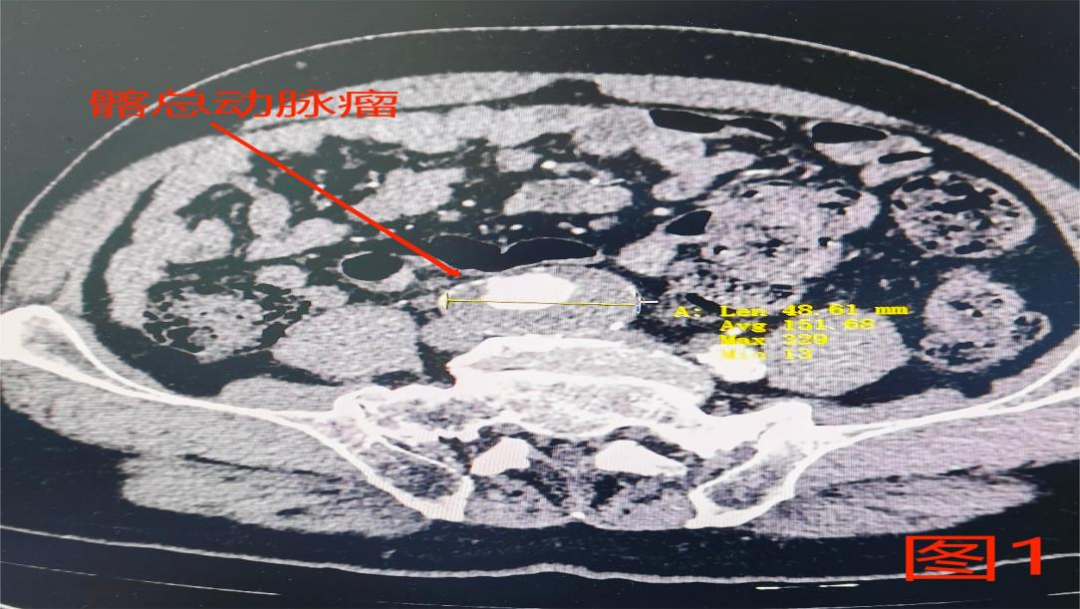

一位老年男性因体检发现髂总动脉瘤,血管外科收入院。完善主动脉CTA回报(见图1):右侧髂总动脉管腔局限性增宽呈梭形动脉瘤样外观,病变最宽处约48mm,提示右侧髂总动脉瘤形成。